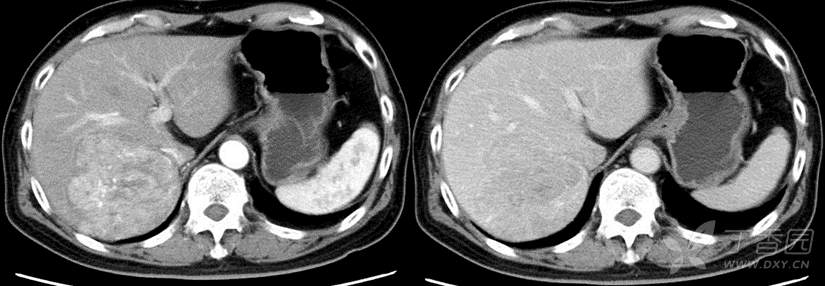

去年11月的一个肝癌患者,片子如上,外科医生第一反应肯定是切除,但是评估以后右半肝切除剩余肝体积不够,右后叶切除安全切缘不能保证(精准肝脏外科理念不但体现在术中,更要体现在术前规划阶段)。提请MDT讨论,用了PD-1+仑伐替尼+放疗降期治疗(放疗范围是右半肝,听放疗L教授说,不但可以控制肿瘤,还能促进左半肝体积代偿增生)。

12月底患者因心肌炎及甲状腺毒症再次入院,MDT讨论后停用免疫治疗,继续口服仑伐替尼降期。到了2月份再次评估,前后一对比明显好多了: